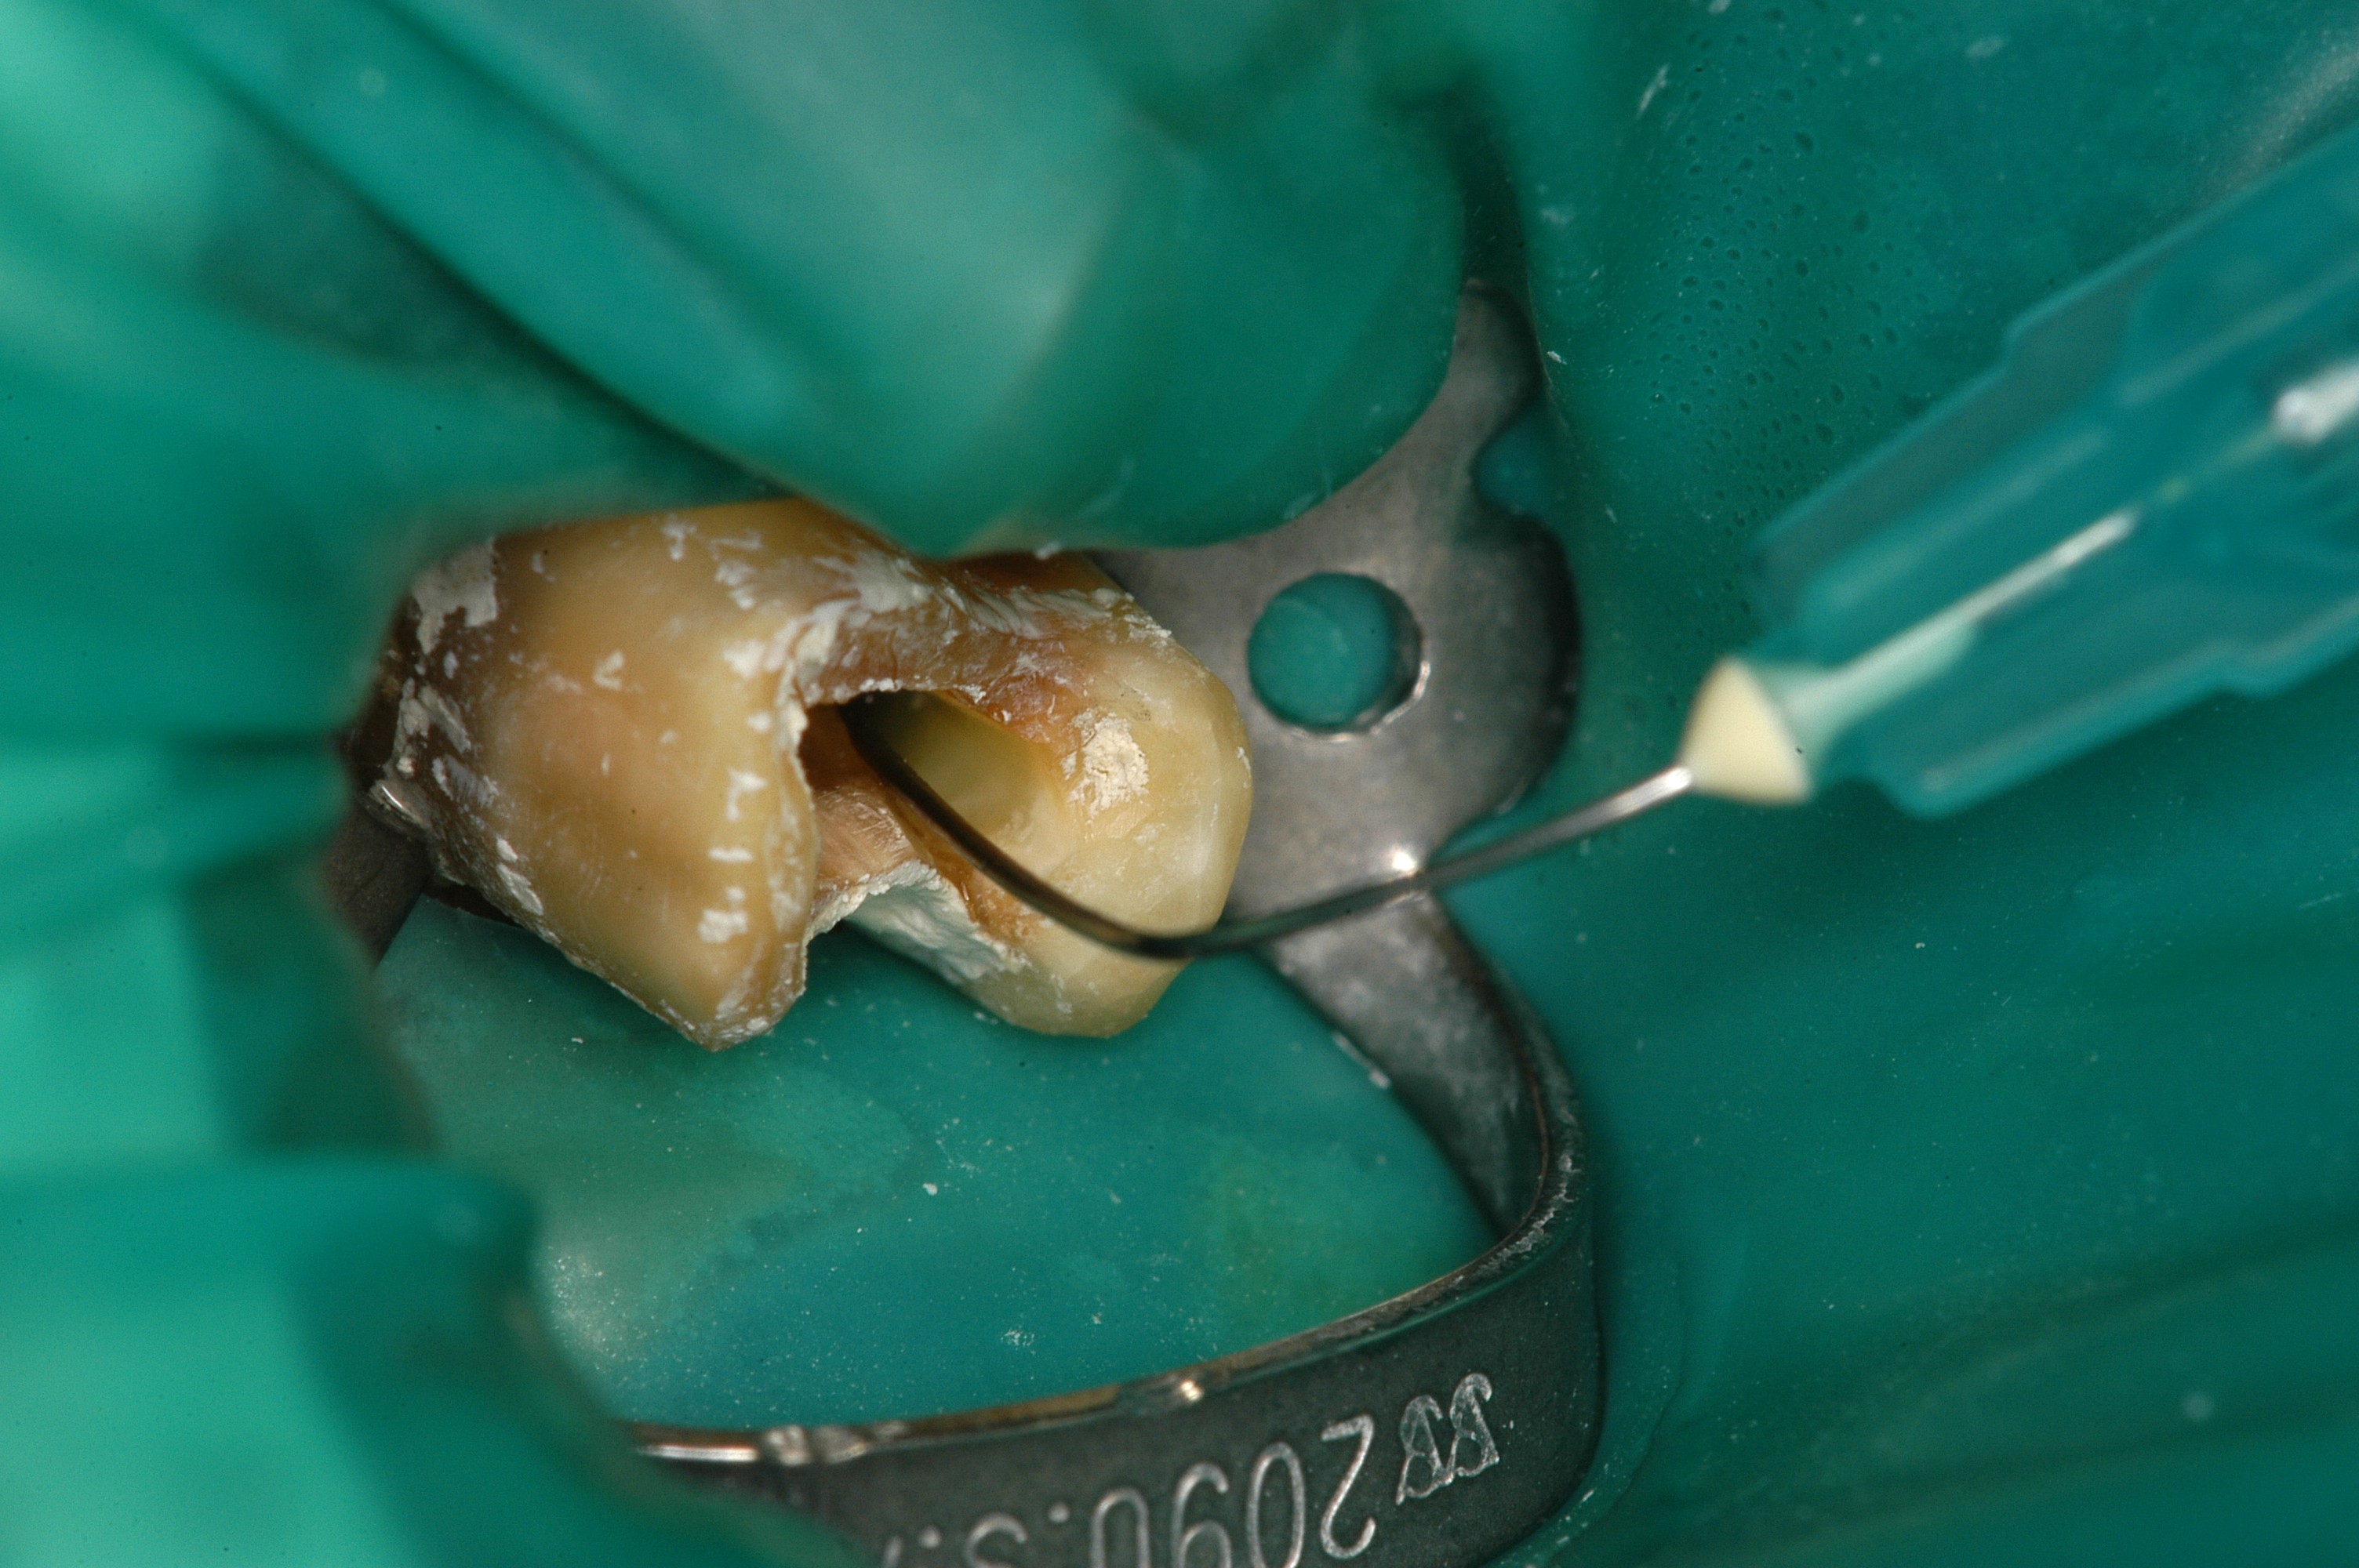

Druckfähiges Bildmaterial zum Download: